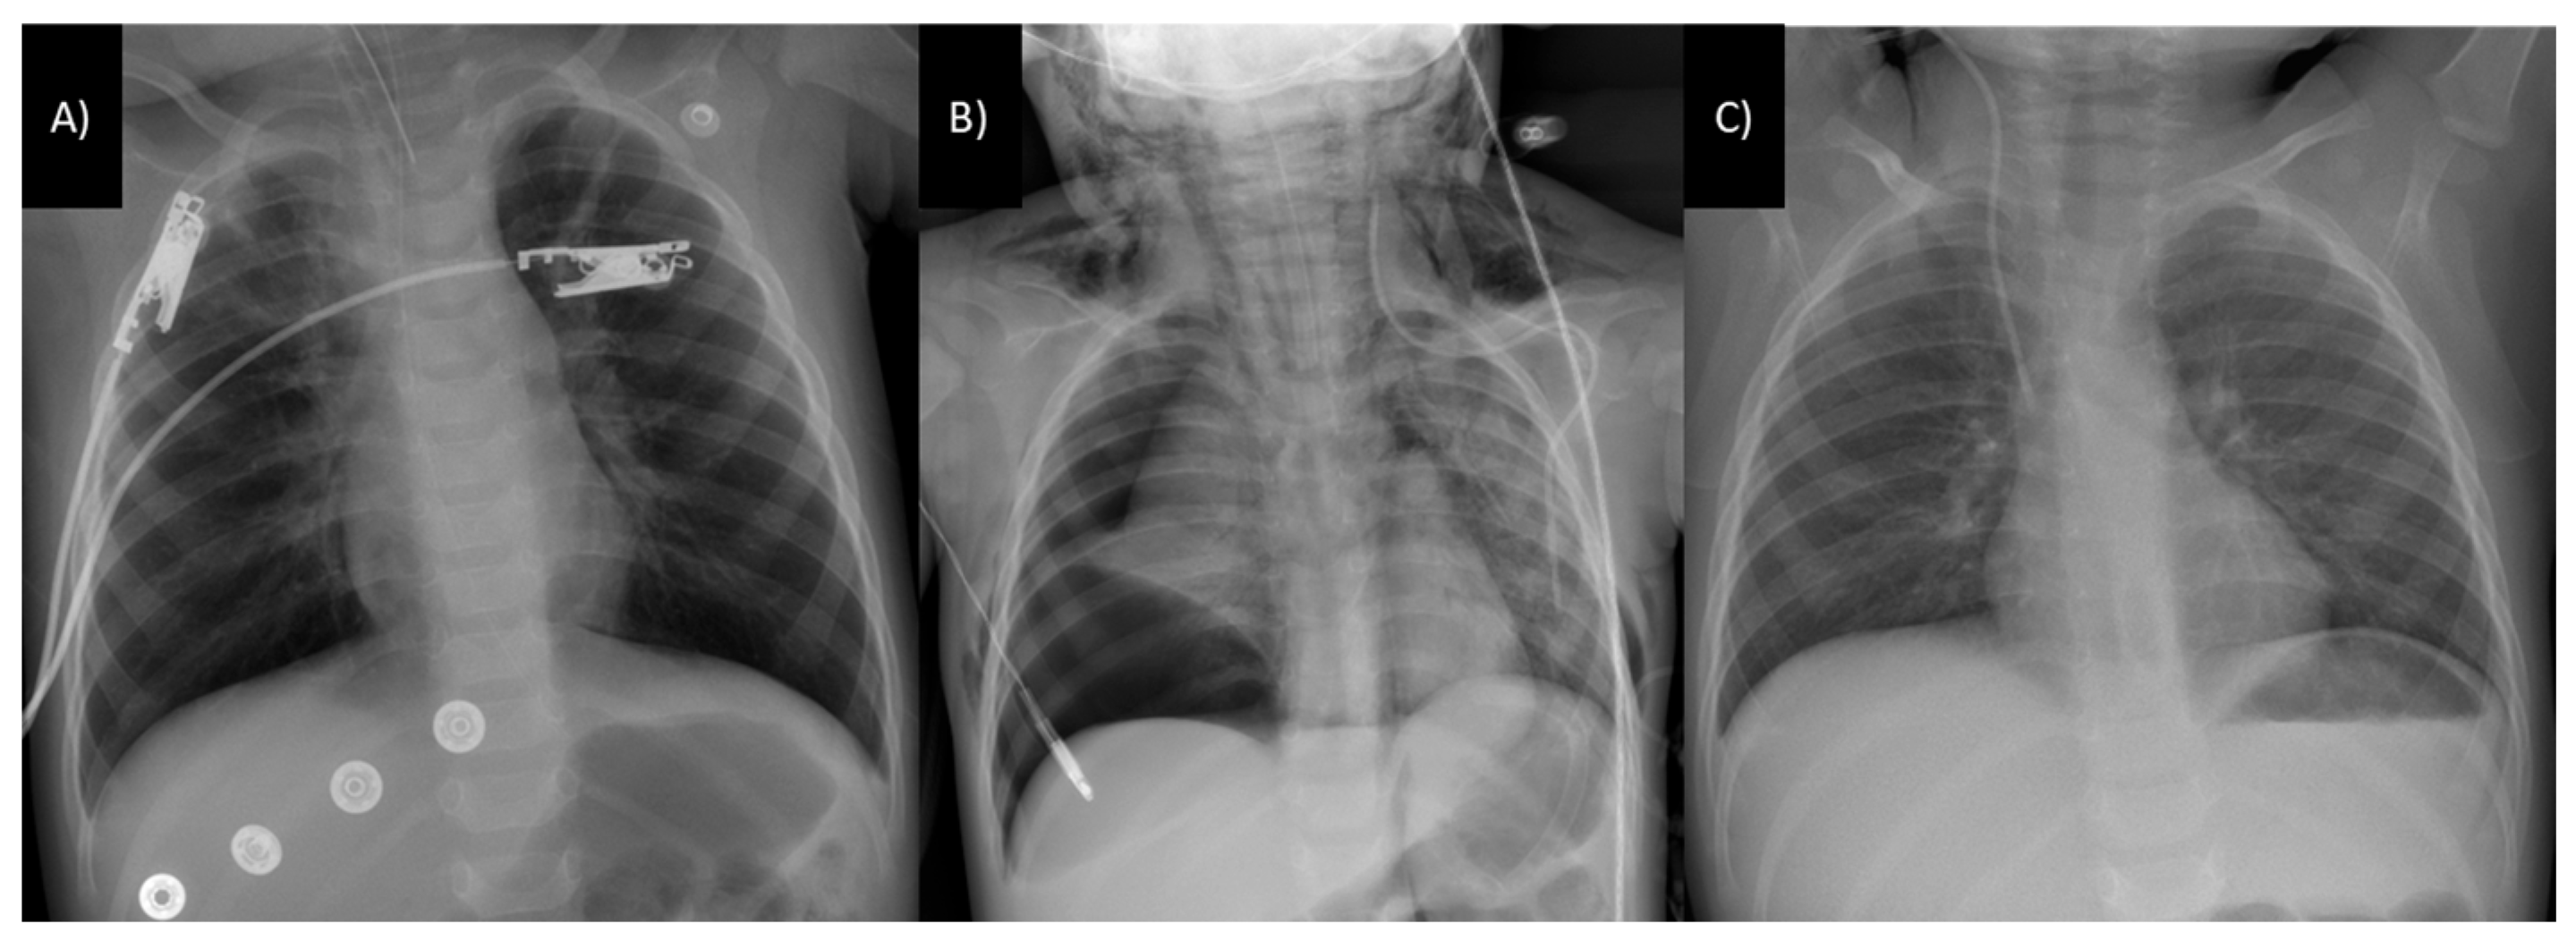

3.3. Respiratory Tract Involvement